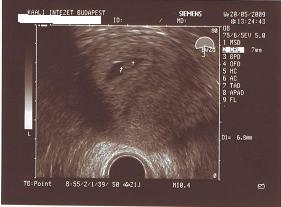

Ma voltam a klinikán! Megvan az időpont jún.16-án lesz a műtét, előtte való nap kell befeküdni!!!!!

Azt mondta hogy megint csinálnak átjárhatóságit és megnézik hogy mizujs odabent, de lehet hogy az egyik petevezetékemet ki kell venni, aminek a vége le van zárva!!!!!!

De lehet hogy mindkettőt!!!!!

Nem azért hogy kiszúrjanak velem, hanem hogy ne legyen egy esetleges méhenkívülim!!!!! :